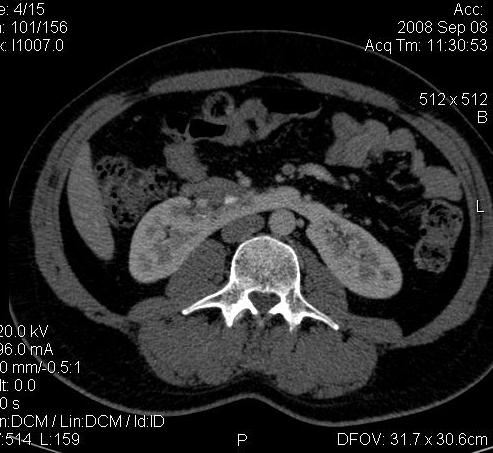

Re: КТ Почек. Почечная колика

Почечная колика; на последнем аксиальном скане чётко виден мелкий (2 мм) камень в устье правого мочеточника.

Dr.Mario писал(а):Почечная колика; на последнем аксиальном скане чётко виден мелкий (2 мм) камень в устье правого мочеточника.

Для невладеющего КТ,очень четка видна аномалия на 3-4х снимках.А вот на 4-м скане в проксим.сегменте цистоида тоже есть гиперденсное точечное образование-не камень случайно?